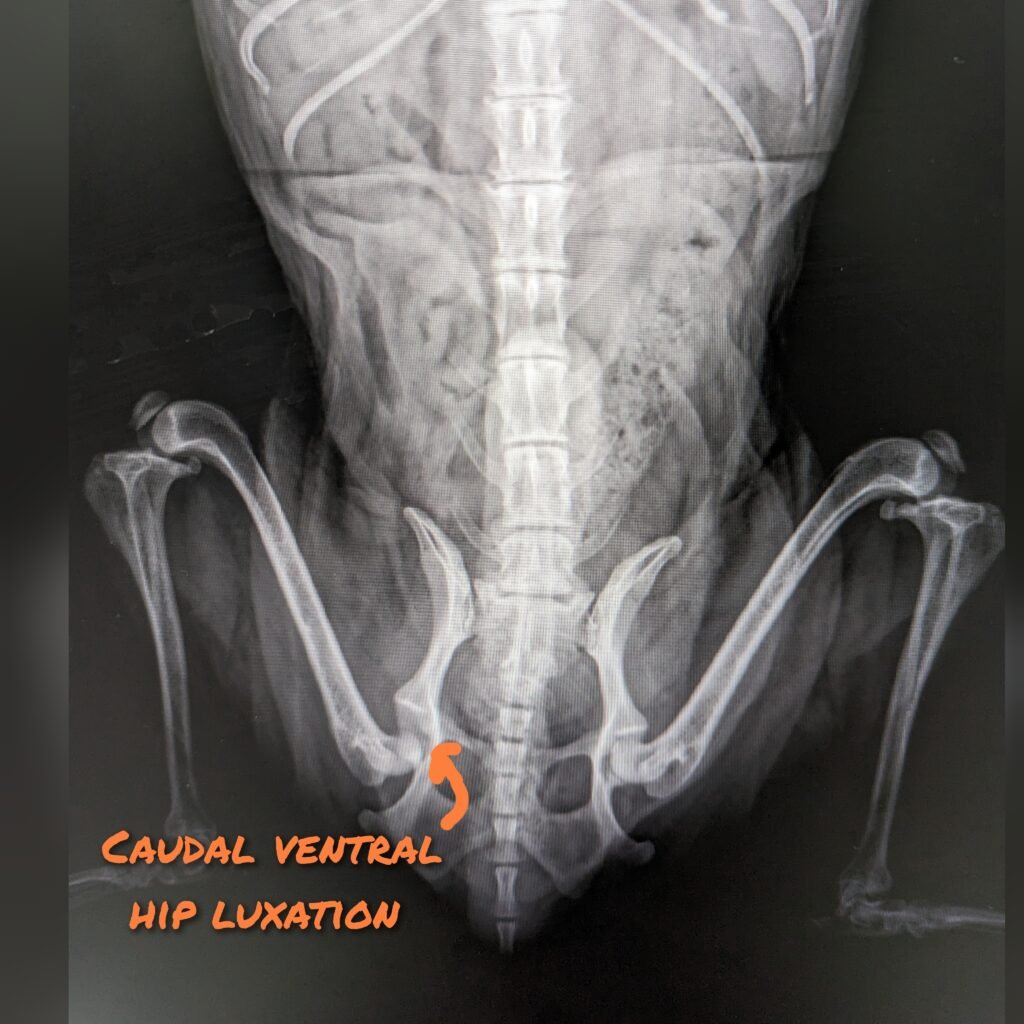

Hip Luxation – caudoventral luxation

Treatment for caudalventral hip luxation is similar to craniodosal luxation. Closed reduction under general anesthesia is recommended for acute, uncomplicated hip luxation. The hind limbs are then placed in hobbles to prevent abduction of the hips for 2 weeks. Cage confinement is also essential for immobilization of the hip. If conservative treatment fails, then surgical options can be considered.

❌Ehmer slings are contraindicated for ventral luxation❌